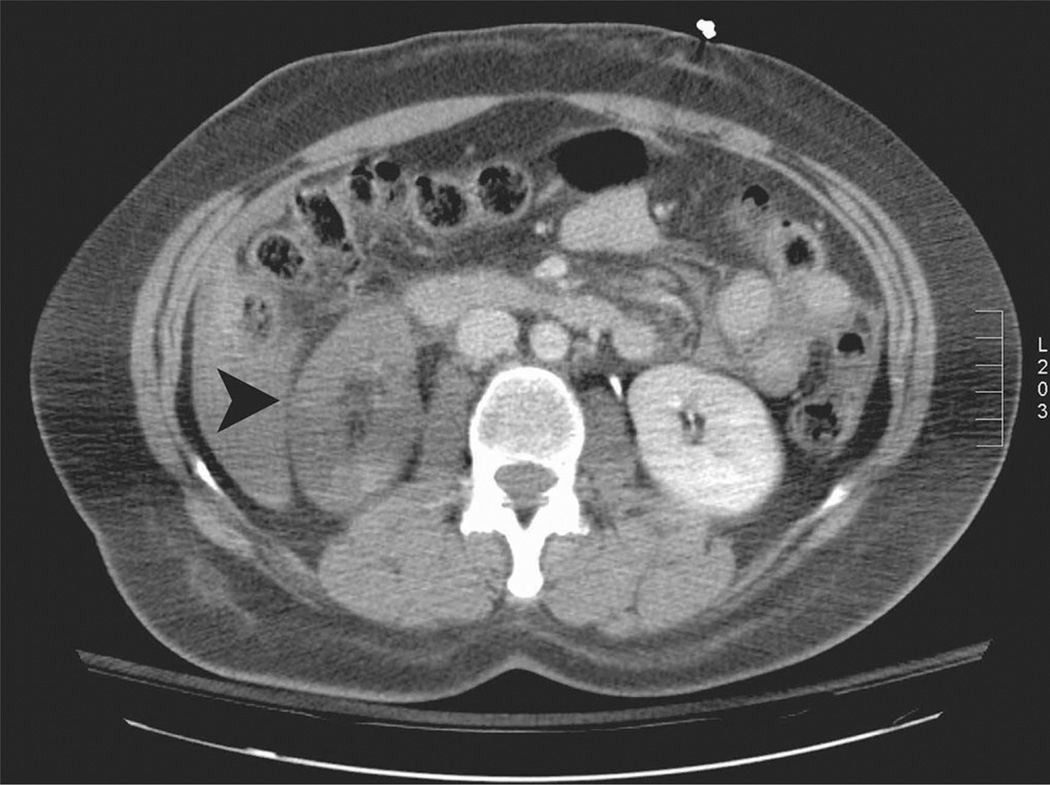

Fig. 1.

Computed tomography scan showing a perfused left kidney and a nonperfused right kidney (arrow).

A 43-year-old female motorcyclist sustained blunt trauma and presented with abdominal, chest, and extremity pain. Physical examination was significant for an acutely tender abdomen. Serum chemistries and hematocrit were within normal limits. Gross blood was not present on Foley catheter insertion, but urinalysis revealed microscopic hematuria. A computed tomography scan showed the right kidney was nonperfused; indicating a grade V injury (Fig. 1). No perinephric hemorrhage or retroperitoneal fluid was noted. In addition, a grade IV liver injury and a grade I splenic laceration were present. After consultation between the urology, trauma, and interventional radiology service, a laparotomy was deemed inadvisable because of the likelihood of massive liver bleeding. A diagnostic angiography, however, showed no active extravasation from the liver and an abrupt cut off of the injured right renal artery (Fig. 2). A hydrophilic guidewire was used to cross the thrombosed vessel. Two overlapping Cordis Genesis PG244B stents (Johnson and Johnson, Warren, N.J.) were deployed on a high-pressure angioplasty balloon. Repeat angiography revealed restored blood flow to the kidney with no residual intraluminal defect (Figs. 3 and 4). The hepatic and splenic injuries were managed nonoperatively. Given this concomitant trauma, no anticoagulation or antiplatelet therapy was initiated after stent placement. On postoperative day three, the patient’s serum creatinine doubled. Renal ultrasound demonstrated an absence of flow to the right renal artery. The patient’s creatinine peaked at 2.8 and later normalized to 1.2. A 1-month follow-up computed tomography scan and lasix MAG-3 renal scan, respectively, showed patchy contrast uptake and 5% relative function in the stented kidney.